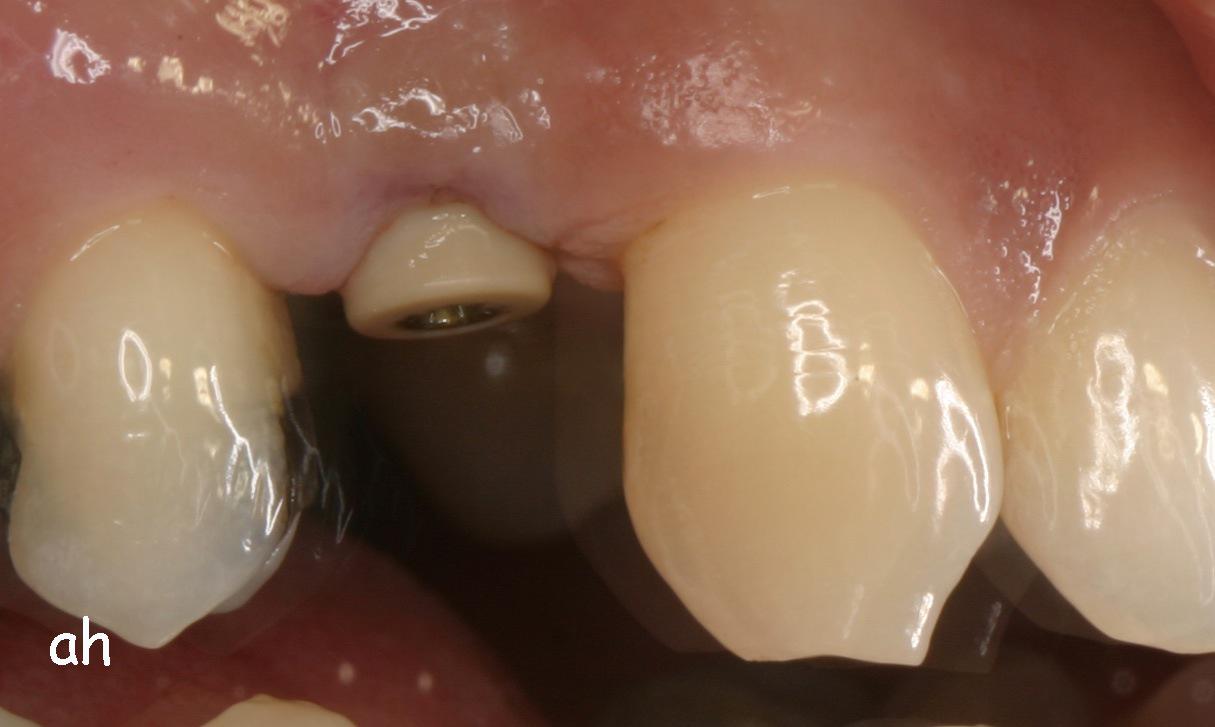

Exemple 7: Un implant au niveau de la deuxième prémolaire inférieure gauche.

Exemple 7: Le moignon vissé sur l'implant.

Exemple 7: La couronne en place

Exemple 7: vue depuis dessus